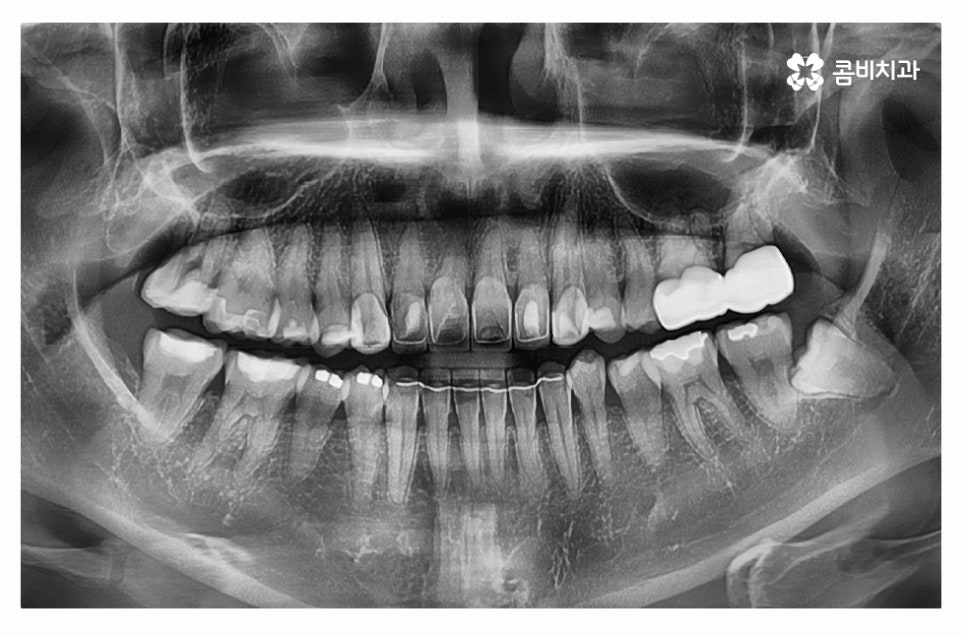

누운사랑니발치의 경우 일반적인 사랑니 발치보다 치료 난이도가

높은 편이기 때문에 고난도 발치에 해당하는 경우

대학병원에 가야 하는 경우도 있지만 우선해야 할 점이라면

사랑니를 3D CT를 활용하여 정확하게 검진해야 하고

누운 사랑니 발치에 대한 이해도가 높고 경험이 풍부한 의사를

찾는 것이 좋으며 해당 진료와 관련된 전문의 자격증이 있는

의료진을 찾는 것도 좋은 방법이라고 할 수 있어요.